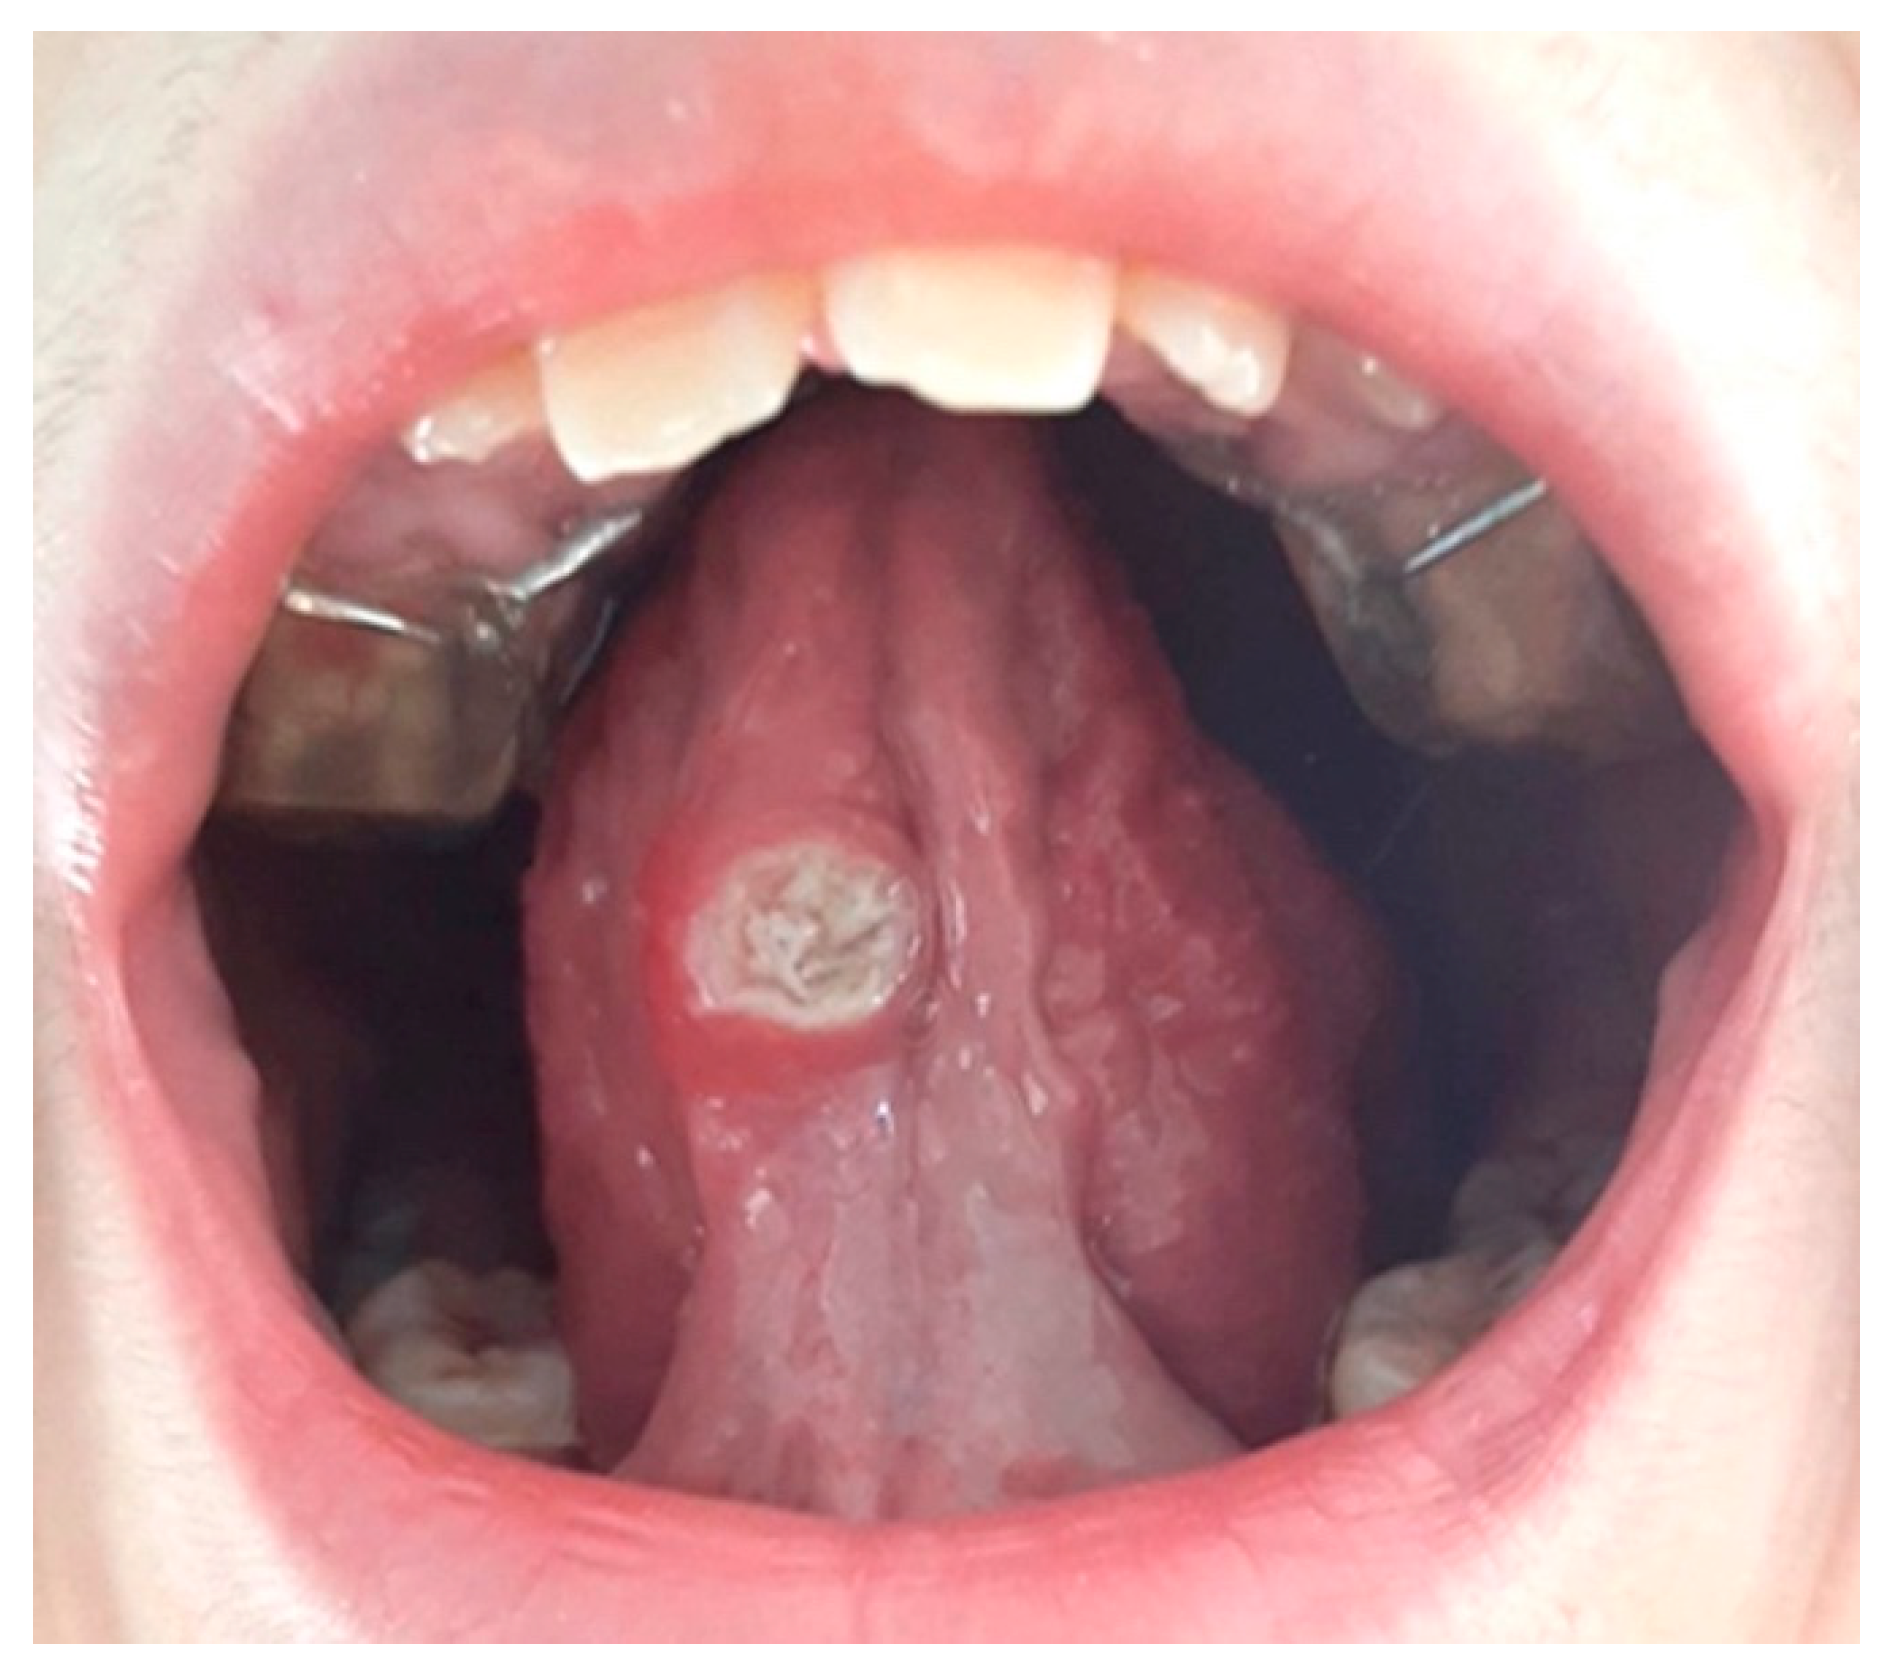

Undoubtedly, the time of evolution of the lesion makes it essential to carry out a biopsy in order to classify the pathology and establish the correct treatment. On the other hand, when we are faced with a large lesion (see Fig. 1), the question arises as to whether we should perform an excisional biopsy or take a representative sample and wait for a histopathological diagnosis.

After histopathological study, the lesion was diagnosed as Traumatic Eosinophilic Granuloma of the Oral Mucosa (TUGSE). This is a rare pathology characterised by the appearance of a single ulcerated lesion that may be asymptomatic and predominantly located on the tongue.18 The appearance of the lesion may be confused with a squamous cell carcinoma, which causes concern for the patient and family members. The lesions are self-limiting, but may take months or up to a year to disappear, which complicates diagnosis and decision-making. This type of lesion was described as its own entity by Saphiro and Juhlin19 in 1970, and when it occurs in infants, it is comparable to the pathology catalogued as Riga-Fede disease and characterised by the presence of traumatic ulcers resulting from the appearance of connatal or early erupting teeth. It usually appears from the 5th decade onwards, which leads to a greater suspicion of carcinoma than when it is a lesion in children 20. In the different studies, no consensus has been found on the existence of a gender predilection21,22,23.

Clinically, the lesion usually has a raised hyperkeratotic border and microscopically it is characterised by a dense infiltrate of T and B lymphocytes, macrophages and mainly eosinophils24 and a tendency to penetrate the underlying muscle.

a) Macroscopic description: 1.3x2 cm round fragment with 1.2 cm ulcer with raised edges and granular central area. Two samples are submitted, one from the central area and one from the periphery.

b) Microscopic findings: infiltrative ulcerative lesion covered with necrotic-fibrinoid material and consisting of an abundant polymorphous inflammatory infiltrate extending in depth around the seromucinous glands and dissociating the muscle fibres. It consists of cells of histiocytic type, lymphocytes, polynuclear neutrophils and abundant eosinophils. PAS and Grocott stains show no fungal elements. No signs of malignancy are observed (see Figures 4–9).